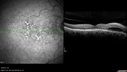

CC: Decreased Vision OS>OD. Activity Affected: reading. Context Onset/Aggravation: on Amsler grid. Other: lines seemed straighter yesterday. Pertinent Negatives: No Floaters. Course: variable, some days better than others. Extended HPI: Pt reports that the left eye is bothering him "a lot" for the past few weeks. He characterizes the vision loss as "distortion." VA OD: cc20/40 OS: cc20/50 PHNI IOP: TP OD: 18 OS: 12 DISCUSSION: Macular Edema OS > OD: The macular edema involves the center of the macula in the left eye and is likely contributing to the patient’s vision loss. The etiology of the macular edema is not clear. The right eye has good vision and no leakage at all on angiography so I will obsere the right side while I treat the left. Serous Macular Detachment OS: The subretinal fluid in the macula is probably responsible for some of the patients vision loss. The etiology of the edema in the left eye is unclear and vexing. There is no subretinal leakage on exam. I am going to try topical anti-inflammatories for a month and see if he improves before considering more aggressive intravitreal therapy. There is also a chance that he has a hypertensive etiology to his problem and I recommended optimizing his systemic status.